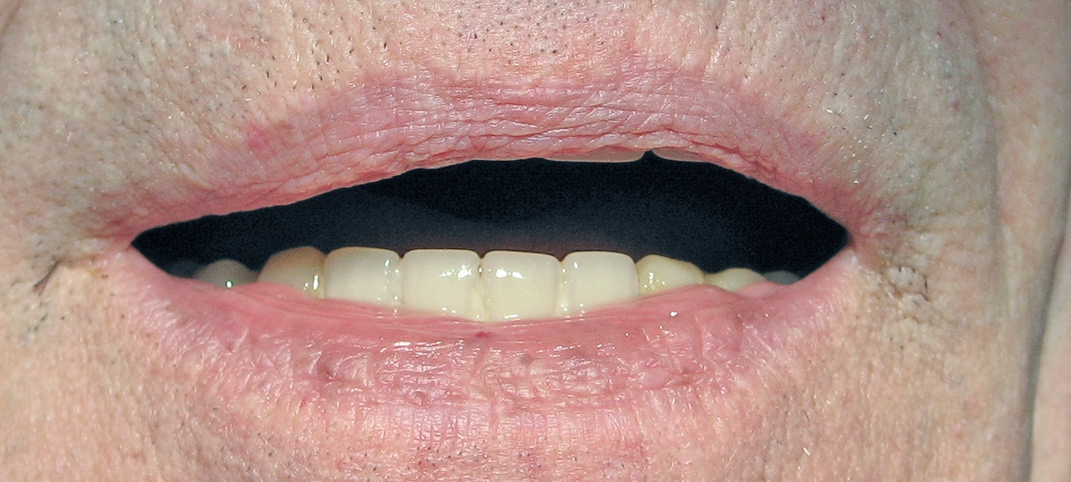

Solche Versorgungen sind in der täglichen Arbeit integriert und eine Standardbehandlung für Situationen, die noch festsitzend realisiert werden können bzw. gewünscht sind. Vorausgesetzt, dass der Ersatz der Zähne für die Unterstützung der Gesichtsweichteile ausreicht, bieten verschraubte Gesamtkiefer-Rekonstruktionen hohen Komfort und Ästhetik, langfristige Gewebestabilität und leichte Pflege und Erweiterbarkeit. Besonders der alternde Patient ist in der Lage eine feste Versorgung zu bekommen und eine optimale Mundhygiene zu betreiben. Kombiniert mit einer digitalen Planung der Chirurgie, Sofortbelastung, Scan des Gesichtsschädels und digitale Abformung kann der Patientenkomfort enorm gesteigert werden.